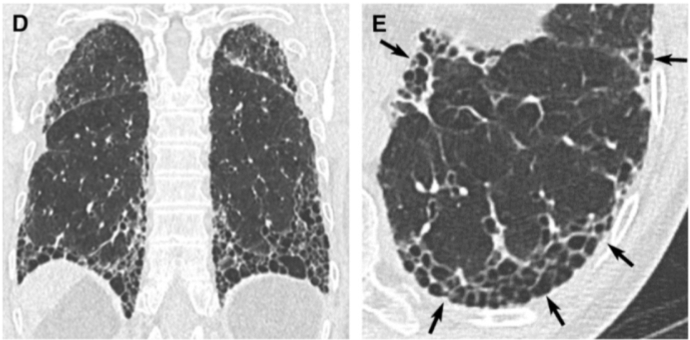

Is this UIP?

This is not UIP because there too much ground glass (too hazy)